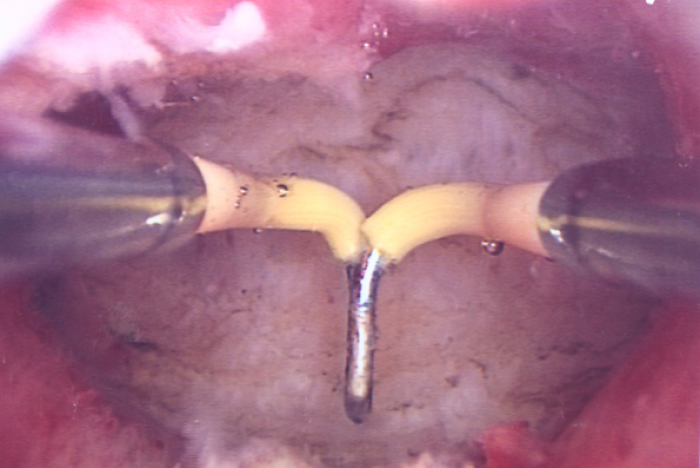

Con este curso conocerás la técnica histeroscópica en consulta, así como la instrumentación histeroscópica disponible en la actualidad. Entenderás las bases del procedimiento diagnóstico y estudiarás el ciclo endometrial normal. Comprenderás la patología funcional del endometrio, además de los fundamentos del manejo de la patología tumoral benigna y premaligna. Por último, descubrirás la técnica histeroscópica quirúrgica en consulta y sus limitaciones.

Curso dirigido a especialistas en obstetricia y ginecología, licenciados en medicina, residentes y tambíen a profesionales de la salud interesados en el estudio y manejo de la patología intracavitaria a través de la histeroscopia. El objetivo principal consiste en justificar la presencia de la histeroscopia en la práctica diaria, intentar difundirla como procedimiento básico en manos de unmayor número de especialistas, actualizar los conocimientos para le manejo habitual del instrumental, conocimientos de las indicaciones y preparación de las pacientes para consultorio y quirófano. Todo ello de la mano de los mejores conocedores nacionales e internacionales de la técnica.

VIDEOS PRÁCTICA CLÍNICA - 2: Histeroscopia diagnóstica. Sonia Martínez

VIDEOS PRÁCTICA CLÍNICA - 4: Cirugías de consultorio. Paloma Lobo